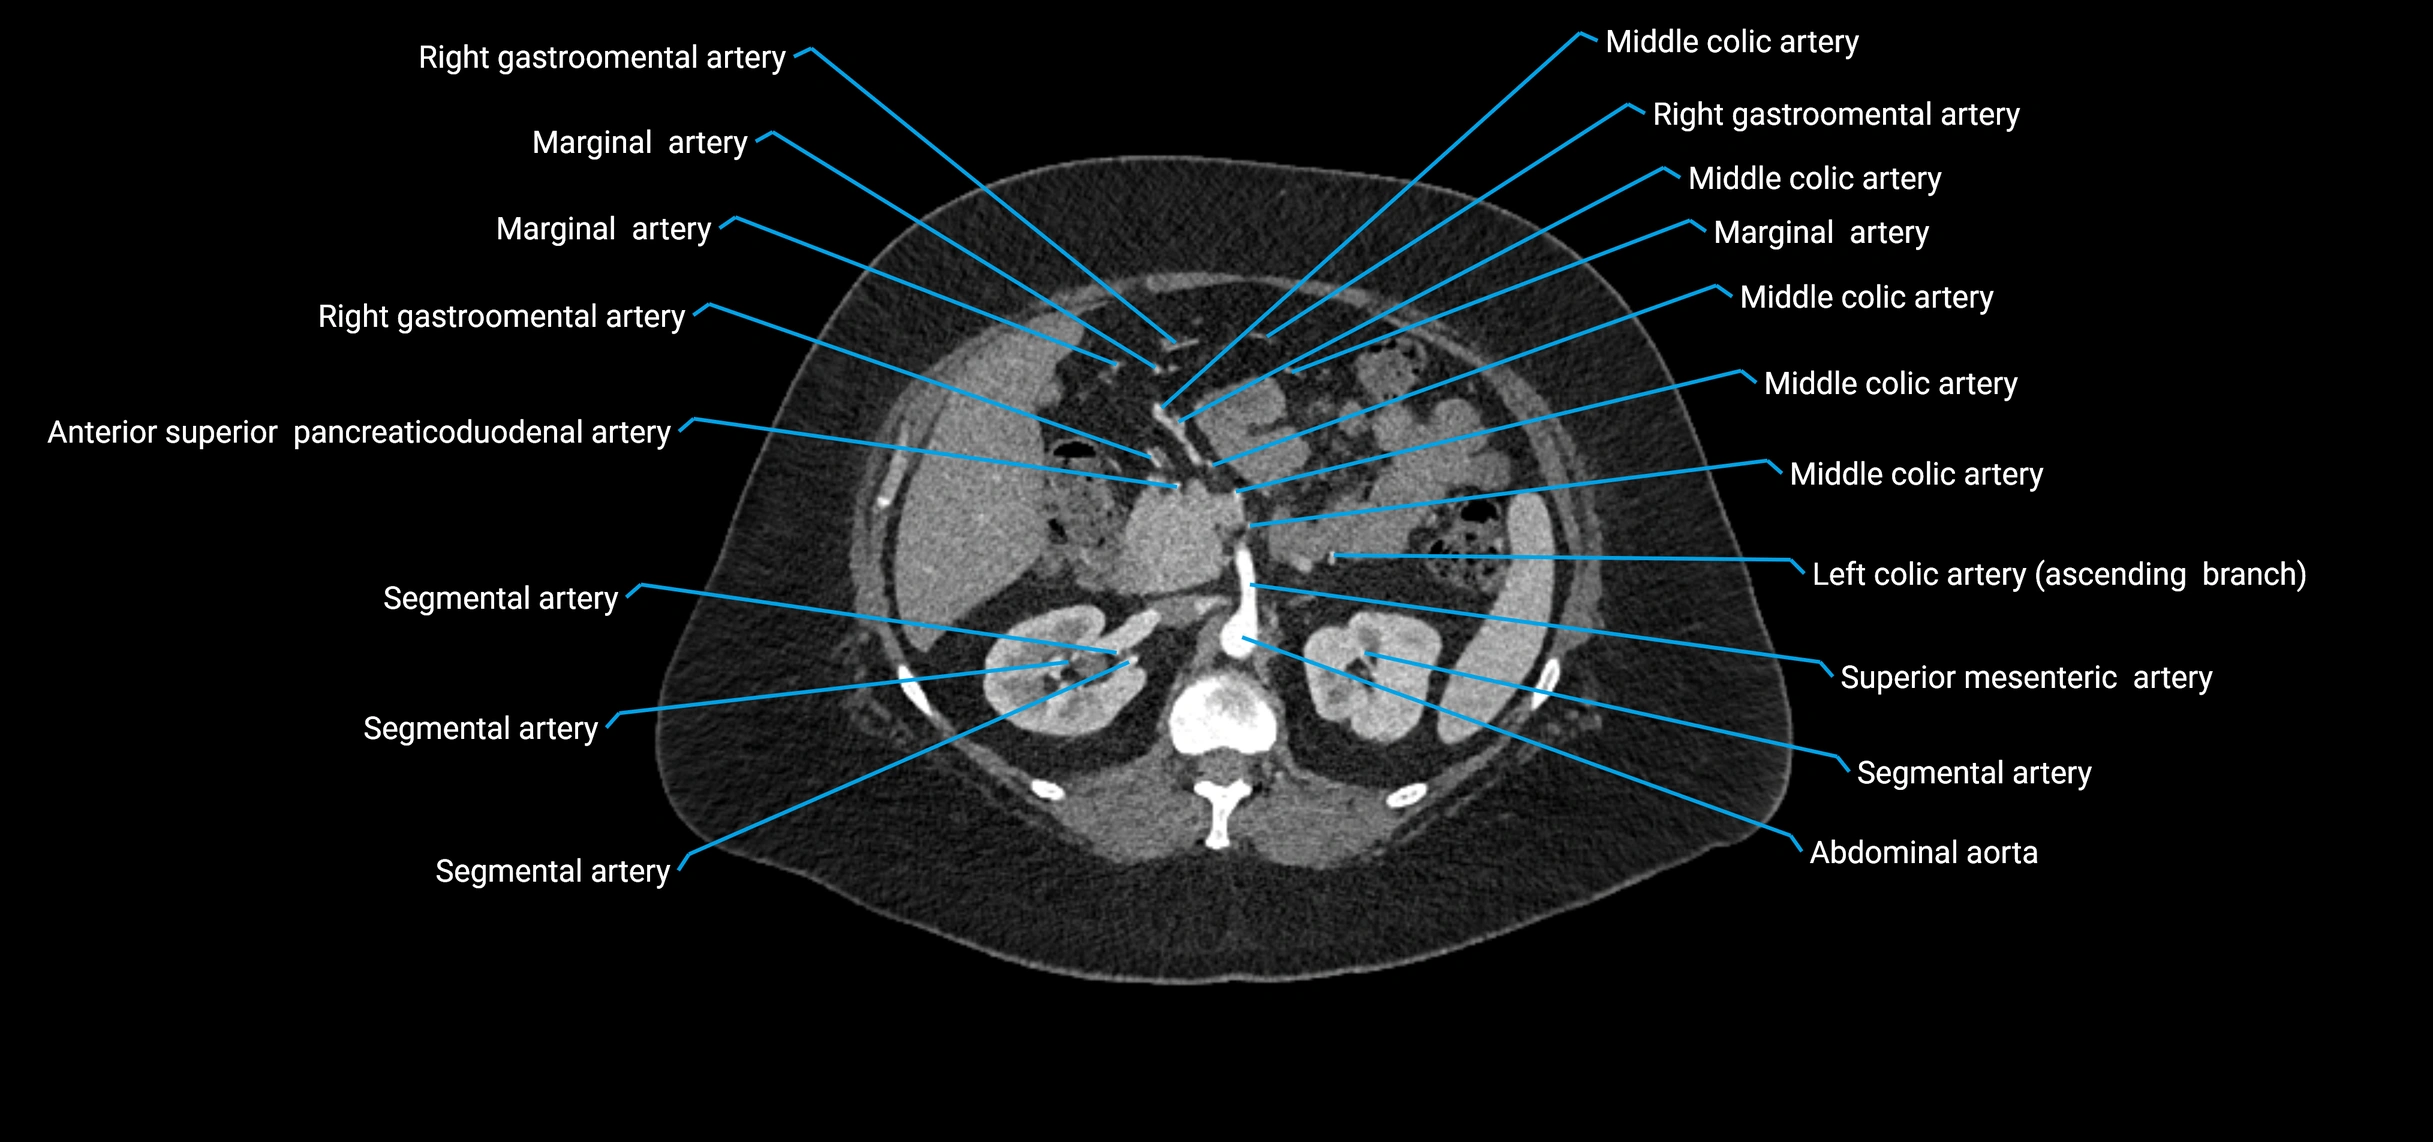

Contrast-enhanced CT (CTA):

• Gold standard for abdominal aortic imaging

• Provides excellent detail of lumen, wall, aneurysm, thrombus, and branch vessels

• Multiplanar and 3D reconstructions help in aneurysm measurement, stent graft planning, and dissection evaluation

• Detects acute rupture, traumatic injury, or occlusion with high sensitivity